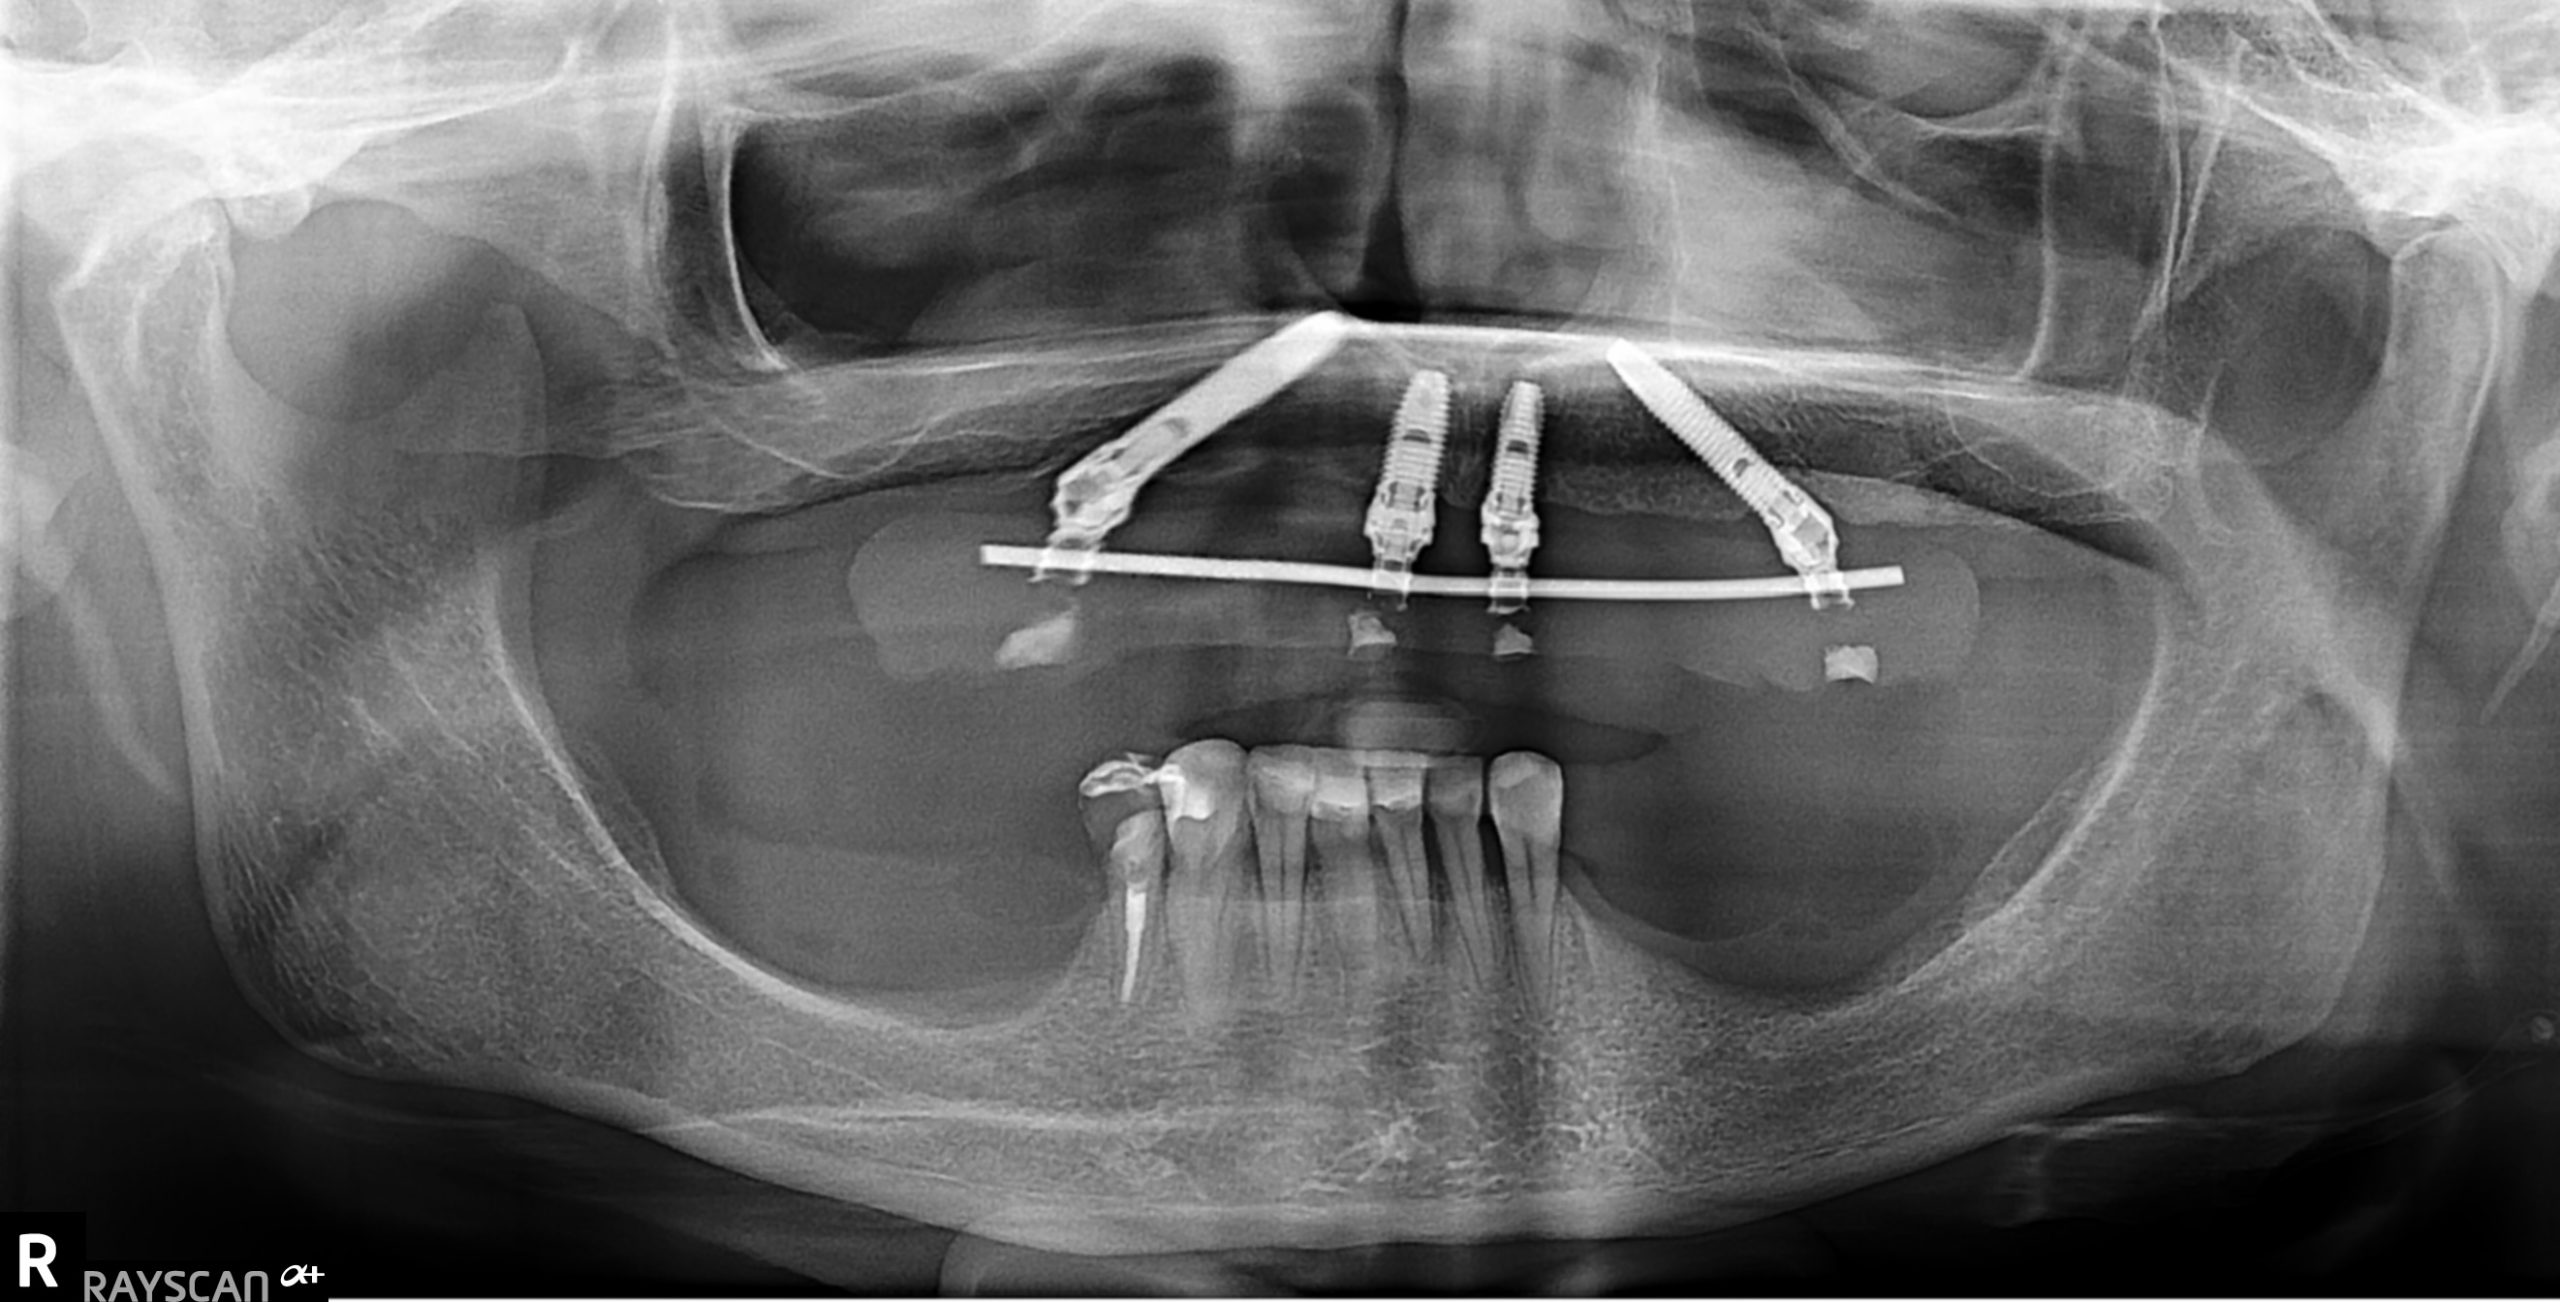

FIG 2